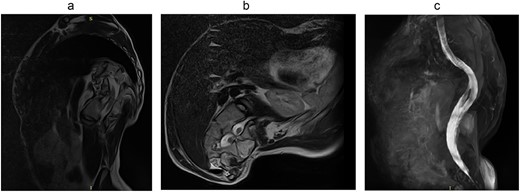

Magnetic resonance imaging (MRI) visualizes the separation of the spinal cord into two arms at the Th11 level (Fig. 5).

Computed tomography (CT) visualizes diastematomyelia in the form of a calcar at the level of Th11, Th12, L1 vertebrae (Fig. 4).